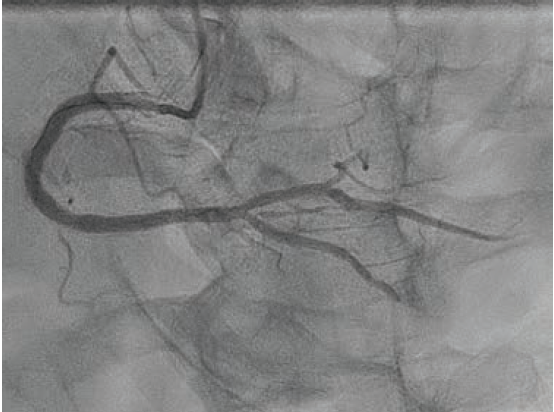

An 80-year-old male with hypertension, dyslipidemia, type 2 diabetes mellitus, chronic kidney disease stage IIIa, and known coronary artery disease (CAD) with recent PCI to the left anterior descending (LAD) artery presented to our emergency department (ED) with recurrent unstable angina. Ten days prior, he underwent coronary angiography for unstable angina and was found to have a 90% mid-LAD lesion that was stented with a 2.5 mm x 28 mm Synergy™ drug-eluting stent (DES) (Boston Scientific). Also present was severe calcific disease of the proximal and mid right coronary artery (RCA) (Figure 1); the plan was for staged PCI of the RCA in 4 weeks. However, prior to the planned procedure and due to recurrent unstable angina, the patient was sent back to the hospital by his primary care physician. On arrival, his electrocardiogram showed no ischemic changes, and serial high-sensitivity troponins were minimally elevated and flat.